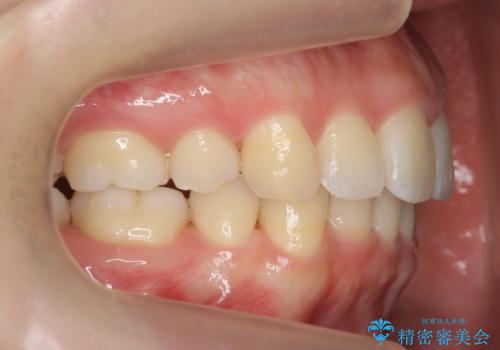

再矯正 昔ワイヤーで治療 前歯の並びを再度きれいに

- 小さいころに小臼歯を抜歯しワイヤー矯正をしたが、すき間が空いてきて、前歯の並びが戻ってしまったとのこと。

インビザラインライトという部分矯正コースで、全体矯正に比べ、比較的安価に治療しました。

前歯の並びが格段にきれいになり、大変喜んでいただけました。